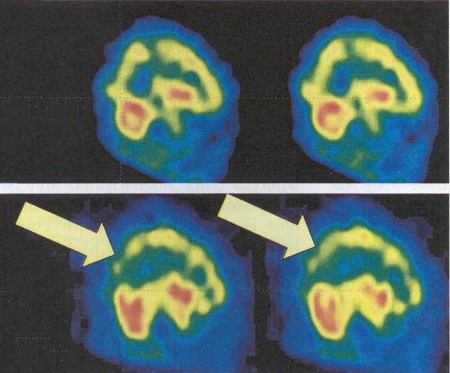

INICIO > Fotogalería > SPECT DEMENCIA DE CUERPOS DE LEWYS.jpg